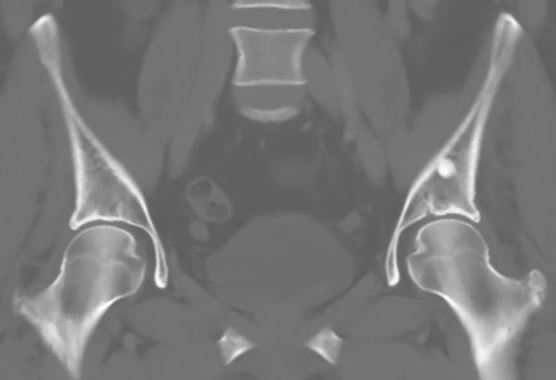

Osteopoikilosis

Rare inherited benign condition characterised by multiple bone islands

AD inheritance, high penetrance

Lesions clustered around joints

- typically arms, legs and pelvis

Malignant transformation extremely rare